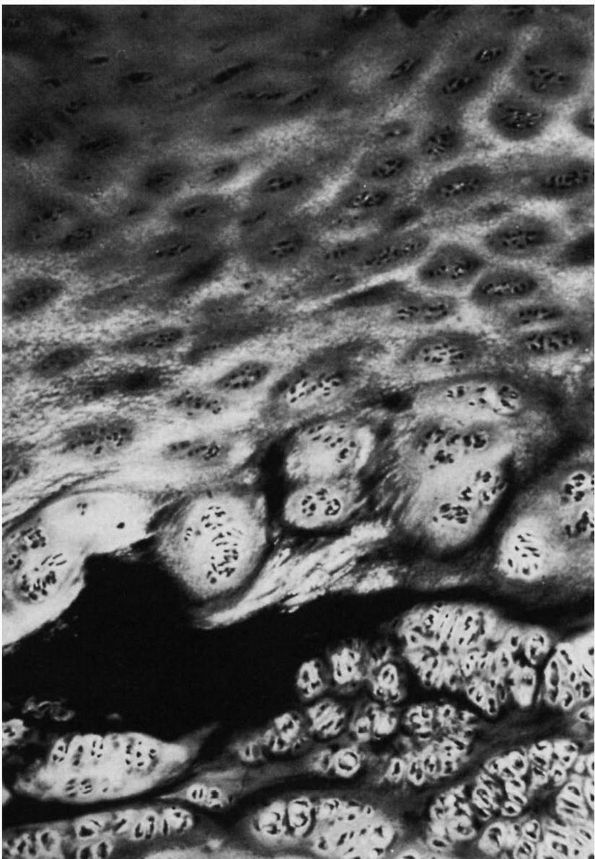

cartilage of patients with LCPD were described as early as 1913 by

Perthes. The superficial zone of the cartilage covering the affected

femoral head is normal but thickened (Figure 15-13).

In the middle layer of the epiphyseal cartilage, however, two types of

abnormalities are seen: areas of extreme hypercellularity, with the

cells varying in size and shape and often arranged in clusters; and in

other areas, a loose, fibrocartilaginous-like matrix. These abnormal

areas in the epiphyseal cartilage have different histochemical and

ultrastructural properties than normal cartilage or fibrocartilage.

Areas of small secondary ossification centers are evident, with bony

trabeculae of uneven thickness forming directly on the abnormal

cartilage matrix.

![]() |

FIGURE 15-13. Anatomic regions of the proximal femur in a growing child. (Weinstein SL. Legg-Calvé-Perthes disease. In: Morrissy RT, Weinstein SL, eds. Lovell and Winter’s Pediatric Orthopaedics, 5th Ed. Philadelphia: Lippincott Williams & Wilkins, 2001:962)

formation with amorphous debris and extravasation of blood. In the

metaphyseal region, enchondral ossification is normal in some areas;

but in other areas, the proliferating cells are separated by a

fibrillated cartilaginous matrix that does not calcify. The cells in

these areas do not degenerate but continue to proliferate without

enchondral ossification. This is evidenced by “tongues” of cartilage

extending into the metaphysis as bone growth proceeds in adjoining

areas (Figure 15-14).